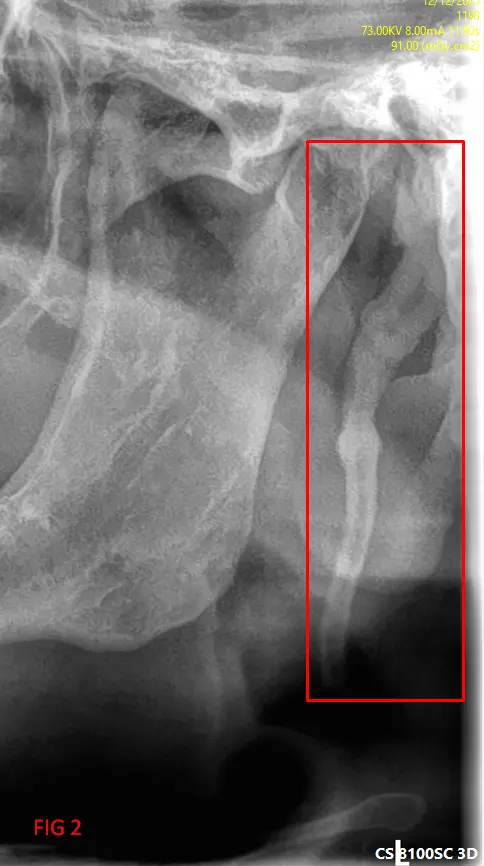

​En el análisis de la ortopantomografía, se identifican estructuras radiopacas bilaterales de morfología alargada. Estas formaciones se extienden desde la base del cráneo (apófisis estiloides) con una trayectoria descendente y anterior hacia el hueso hioides (FIG 1, 2 y 3). Basándose en las características imagenológicas, se concluye que se trata de una osificación bilateral del ligamento estilohioideo, un hallazgo que suele presentarse de forma incidental